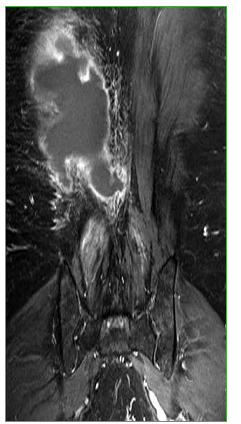

Figura 3.

Resonancia magnética, corte axial, nivel L1. Se observa una colección subaponeurótica en relación con la musculatura paraespinal derecha.